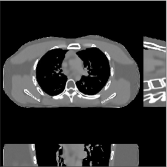

This section compares the reconstruction quality and runtime among the proposed MBIR method, PWLS-ST-, and other three MBIR methods, PWLS-EP, PWLS-DL, and PWLS-ST-. Table I shows that, for both 2D and 3D sparse-view CT reconstructions of the XCAT phantom, the proposed PWLS-ST- model outperforms PWLS-EP and PWLS-ST- in terms of RMSE. In addition, PWLS-ST- using a square transform (of size ) achieves lower RMSE than PWLS-DL using an overcomplete dictionary (of size ) for 2D sparse-view reconstructions. Fig. 3(a) and Fig. 4 show the reconstructed images for 2D and 3D phantom experiments, with different reconstruction models and different number of views. (See the corresponding error maps in the supplement.) The proposed PWLS-ST- consistently gives more accurate image reconstructions compared to other MBIR methods. Specifically, PWLS-ST- has smaller errors in the heart region (see zoom-ins in Fig. 3(a)) of 2D reconstructions than PWLS-DL and PWLS-ST-. In addition, compared to PWLS-ST-, PWLS-DL and PWLS-ST- have some ringing artifacts around the edges with high transition, e.g., edges between air and soft tissues. (See a comparison of profiles of PWLS-ST- and PWLS-ST- in the supplement.) In particular, PWLS-ST- and PWLS-DL give more visible ringing artifacts for 2D reconstruction from fewer views, and PWLS-ST- has these ringing artifacts for 3D reconstructions regardless of the number of views (see zoom-ins in Fig. 4). Table II reports runtimes of different MBIR methods in reconstructing the -views XCAT phantom scan. (FBPConvNet is a non-MBIR method and its runtime for processing a image is approximately one second with a TITAN Xp GPU.) While providing better reconstruction quality, the proposed Algorithm 1 of PWLS-ST- has shorter runtime compared to the algorithms of PWLS-DL and PWLS-ST- in Section III-A. Similar to the PWLS-EP algorithm, the reconstruction time of the PWLS-DL, PWLS-ST-, and PWLS-ST- algorithms can be further reduced by using ordered subsets [51].

Fig. 3(b) shows that when tested on the clinical scan data, the proposed PWLS-ST- method improves reconstruction quality in terms of noise and artifacts removal (e.g., see zoom-ins for soft-issue regions), and edge preservation (e.g., see zoom-ins for bone regions), compared to PWLS-EP and PWLS-ST-. Compared to PWLS-DL, PWLS-ST- achieves comparable image quality, but requires less computational complexity.

| (a) 2D fan-beam CT experiments |

| (b) 3D axial cone-beam CT experiments |